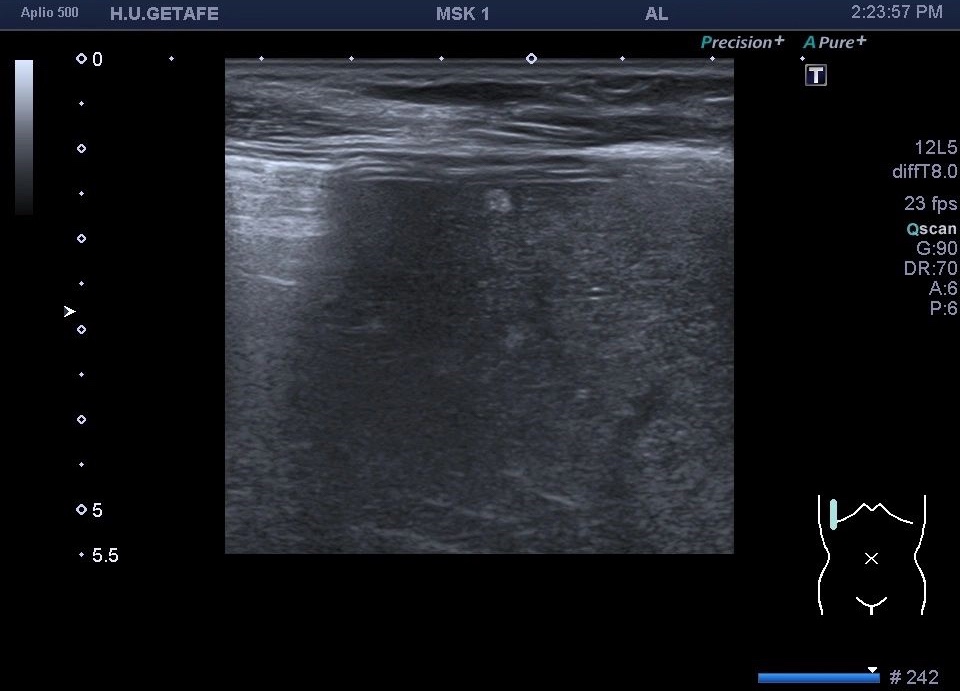

329. Hemangioma hepático. Vista con Sonda lineal.

Hiperecogénicas, redondas u ovaladas, de brillo variable, menores de 3 cms.

Pero en esta ocasión te quiero mostrar una cosa muy a tener en cuenta. En este caso es un estudio muscular dorsal y como hallazgo casual encontramos un montón de micro hemangiomas todos menores de 5 mm y que se hacen visibles por el uso de la sonda lineal de alta frecuencia.